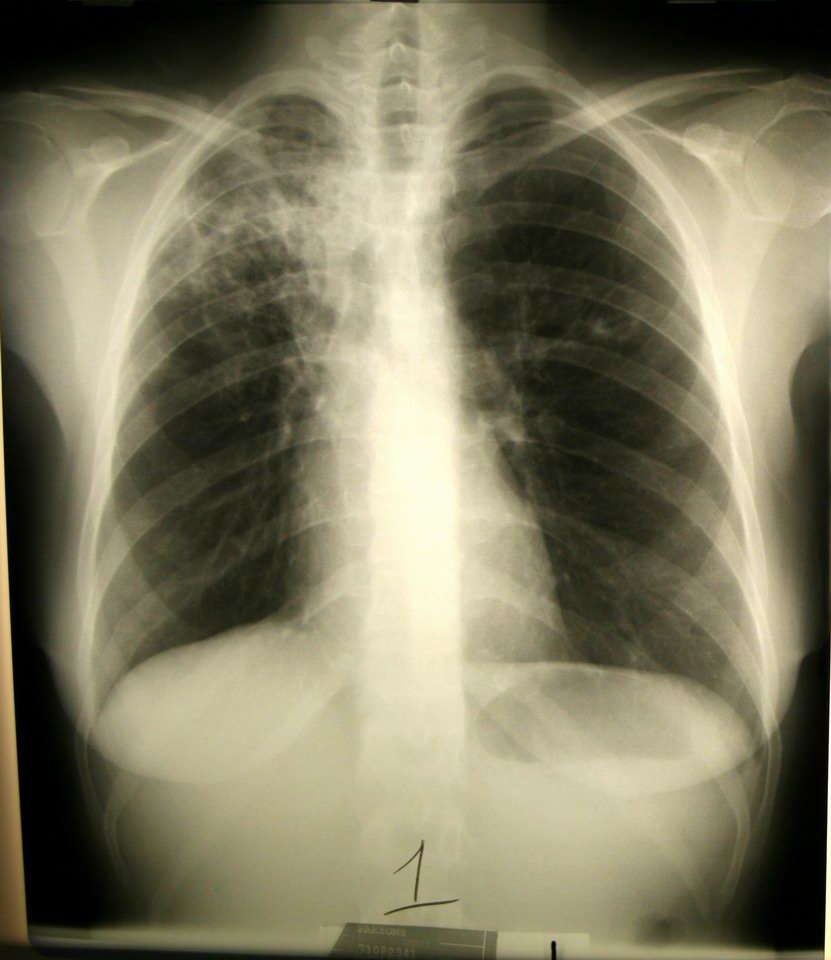

TB in the right upper lobe |